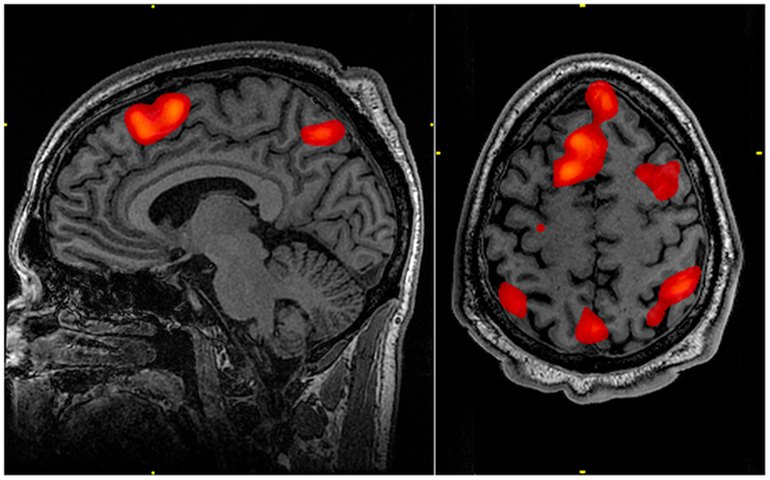

De acordo com a Associação Brasil Huntington (ABH), trata-se de uma doença hereditária rara, neurodegenerativa, que afeta o sistema nervoso central, causando alterações dos movimentos, do comportamento e da capacidade cognitiva. A enfermidade atinge homens e mulheres de todas as raças e grupos étnicos, e os primeiros sintomas costumam aparecer, principalmente, na faixa dos 30 aos 50 anos de idade. A doença é fatal e se desenvolve gradualmente, com duração média de 15 a 20 anos.

A doença de Huntington, ainda de acordo com dados da associação, afeta uma em cada 10 mil pessoas na maioria dos países europeus. Não existem estatísticas oficiais no Brasil, mas estima-se que haja de 13 mil a 19 mil portadores do gene e de 65 mil a 95 mil pessoas em risco.